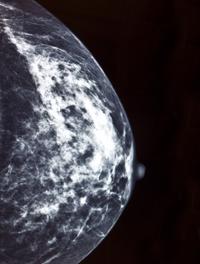

L’amplification et la surexpression de l’oncogène HER2 (human epidermal growth factor receptor 2) sont présentes dans environ 20 % [...]